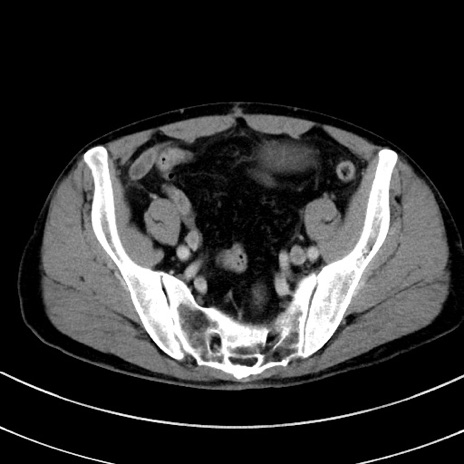

冠状断像

【症例】 60歳代男性

【主訴】 黒色吐物

【現病歴】 4日前から嘔気自覚、2日前の朝食後にも嘔気あり、自分で手で嘔吐反射起こし嘔吐したところ血が混ざっていたため受診。

【既往歴】 5年前汎発性腹膜炎を伴う急性虫垂炎で手術、高血圧、前立腺肥大症、高脂血症

【身体所見】 腹部正中に手術癩痕あり 腹部平坦・軟圧痛なし膨満感あり

【データ】WBC 8400、CRP 4.54